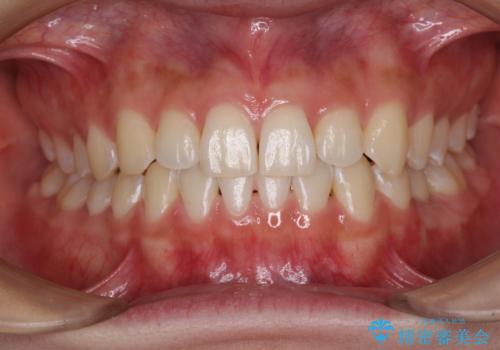

奥歯で噛みたい インプラントによる欠損補綴治療

自分の歯のように噛めるようにしたいとのことで、インプラントによる欠損補綴治療を行うこととしました。